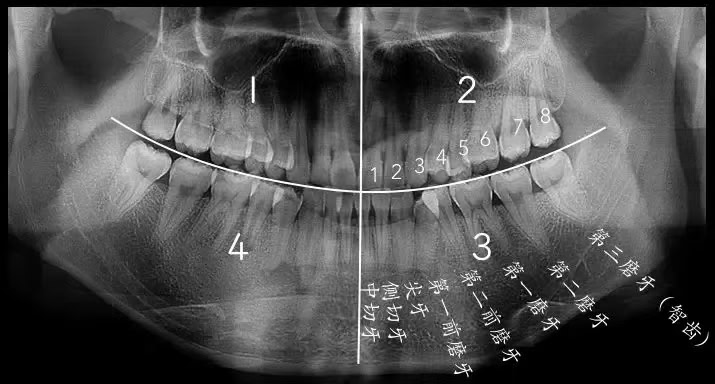

- X光片是評估智齒狀態的重要工具。通過X光片,牙醫師可以了解智齒的實際位置、方向、鄰近牙齒與顎骨的關係,以及是否存在潛在的問題如牙根吸收、囊腫或腫瘤等。

根據阻生智齒的位置和方向,拔除的難度和風險也會有所不同。垂直阻生相對較易處理,而近中阻生或遠中阻生可能需要更複雜的手術程序。阻生智齒的確切類型往往需要通過X光片或CBCT(錐形束計算機斷層攝影)等影像學檢查來確定,以便醫生能正確評估情況並規劃適當的治療方案。